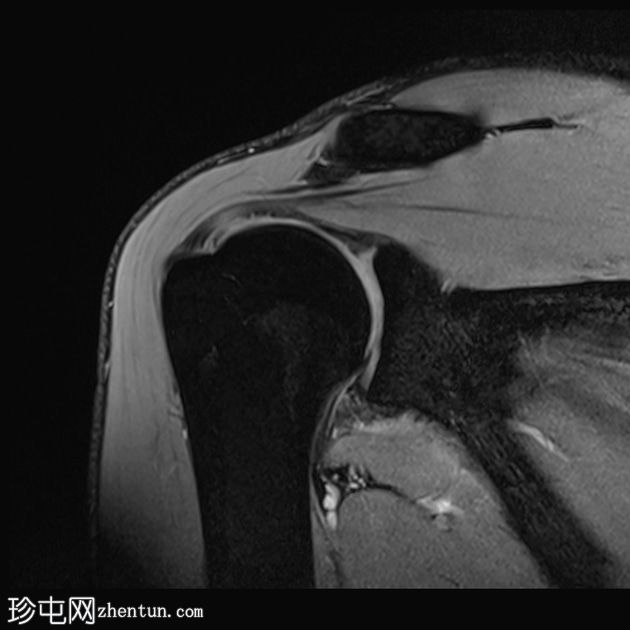

冠状位PD序列

脂肪抑制序列

肱骨头后外侧骨缺损,伴有骨髓挫伤,符合近期肩关节前脱位引起的急性Hill-Sachs损伤。

前下盂唇撕脱,骨膜附着完整,提示软性Bankart损伤。

肩胛盂下韧带前束在盂肱关节附着处断裂,符合GAGL(肩胛盂下韧带)的特征,盂肱关节下方可见关节囊外积液,并伴有盂唇旁囊肿。